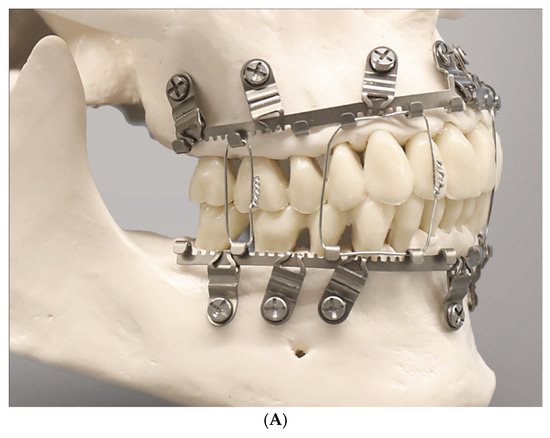

The OmniMax MMF System (Zimmer-Biomet, Jacksonville, FL, USA) is a bone-anchored MMF system and is composed of preformed arch bars (plates) and locking screws based on the same basic principle as other hybrid systems (Figure 3). The market release was in 2016.

Figure 3.

Arrangement of OmniMax arch bars (plates) for application on the mandible and maxillae together with self-drilling locking screws. The plates are preformed by in-plane bending into slight curves. The screws are placed for fixation in the anterolateral transition and the posterior portion of the jaws. At best, no more than two slots in sequence are left empty. Source/origin: Photograph collection—C.P. Cornelius.

The embodiment of the OmniMax arch bars is an in-plane-bent or curved plate, respectively, that carries 12 horizontal slots rising along its length (Figure 3) to accept the bone retaining screws (OmniMax Device ID K143336, Biomet Microfixation OmniMax MMF System, US Patent No 2015/0297272 A1—22 October 2015 [35], Zimmer OmniMax Brochure—Last Internet access February 2025). These screw slots have an elongated oval shape and are organized inside six mounting tabs, each of them enclosing a pair of such slots with a supporting strut in between. Five U-shaped notches between the mounting taps interrupt the longitudinal plate profile and provide a segmental geometry of six uniform sections.

The core diameter of the annular groove is larger than the diameter of the second thread set and is sized for a tight fit within the beveled rims of the slot aperture of the plate (arch bar) (Figure 3 and Figure 4). These properties of the OmniMax screw are the basis for the plate’s standoff feature, which creates a gap between the plate and the gingivo-mucosal surface.

Figure 4.

(A) Clinical case example—intraoperative view of Zimmer Biomet OmniMax MMF devices divided into 4 segments for treatment of a triple mandibular fracture—bilateral condylar base and symphyseal midline. A dental splint (Titanium Trauma Splint, Medartis, Basel, Switzerland) resin bonded (acid etching technique) to the outer surfaces of the teeth of the anterior maxillary arch supports the repositioned medial upper incisors. The two maxillary segments represent the shortest possible plate variant consisting of a single mounting tab containing two slot apertures, with 2.0 four-hole miniplate visible in open anterior vestibulum approach. Of note: the standoff mechanism has been implemented for all screws—annular screw grooves fully seated in the slots. (B) Previous case cont’d. Postoperative panoramic X-ray after placement of OmniMax arch bars, ORIF—via transoral vestibular and preauricular transparotid approaches. Miniplate fixation of the condylar base fractures. Four-hole superior border (tension band) miniplate fixation in combination with a six-hole 2.4 inferior border plate. The arch bar retaining screws appear inserted correctly in the interradicular spaces. Source/origin: Photograph collection—C.P. Cornelius.

During continuous insertion of an OmniMax self-drilling screw, the second thread portion will engage the rim of the slot aperture. Owing to the different lead of the threads, with further advancement into the bone, the plate will be raised towards the head of the screw until the rim of the slot will be finally seated into the annular retention groove of the screw and held there by tight friction. For the plate, once seated within the screw’s locking groove, the standoff height can be tuned by turning the screw out of or into the bone. The gap can be further established and adjusted without a spacer tool.

The in-plane pre-bent curvature of the plates (arch bars) and the segmentation at the side of the notches conceivably facilitates the contouring to the anatomy of the mandible or maxilla.

Within the aperture of a slot, the screw position can be slid horizontally across a range of about 5–6 mm. Depending on its length, a minimal number of four screws per bar (Figure 3 and Figure 4A,B) or of two for a single section bar-segment (Figure 5A,B) is required to provide rotation stability.